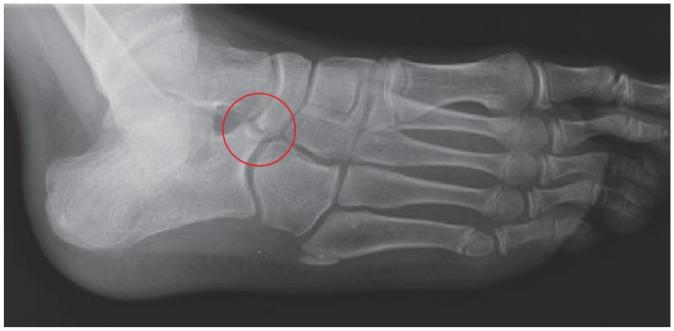

A tarsal coalition is an abnormal connection between two or more tarsal bones caused by failure of mesenchymal segmentation.The two most common tarsal coalitions are calcaneonavicular coalition (CNC) and talocalcaneal coalition (TCC). Both CNC and TCC can be associated with significant foot and ankle pain and impaired quality of life; there may also be concomitant foot and ankle deformity.Initial, non-operative management for symptomatic tarsal coalition commonly fails, leaving surgical intervention as the only recourse.The focus of this article is to critically describe the variety of methods used to surgically manage CNC and TCC. In review of the pertinent literature we highlight the ongoing treatment controversies in this field and discuss new innovations.The evidence-based algorithmic approach used by the authors in the management of tarsal coalitions is illustrated alongside some clinical pearls that should help surgeons treating this common, and at times complex, condition. Cite this article: 2020;5:80-89. DOI: 10.1302/2058-5241.5.180106.

跗骨联合是由于间充质节段化失败导致两块或多块跗骨之间的异常连接。最常见的两种跗骨联合是跟舟联合(CNC)和距跟联合(TCC)。CNC和TCC都可能伴有严重的足踝疼痛和生活质量受损;也可能伴有足踝畸形。对于有症状的跗骨联合,最初的非手术治疗通常无效,手术干预成为唯一的选择。本文的重点是批判性地描述用于手术治疗CNC和TCC的各种方法。在回顾相关文献时,我们强调了该领域持续存在的治疗争议并讨论了新的创新方法。作者在跗骨联合管理中使用的循证算法方法与一些临床要点一起展示,这些要点应有助于外科医生治疗这种常见且有时复杂的病症。引用本文:2020;5:80 - 89。DOI: 10.1302/2058 - 5241.5.180106。